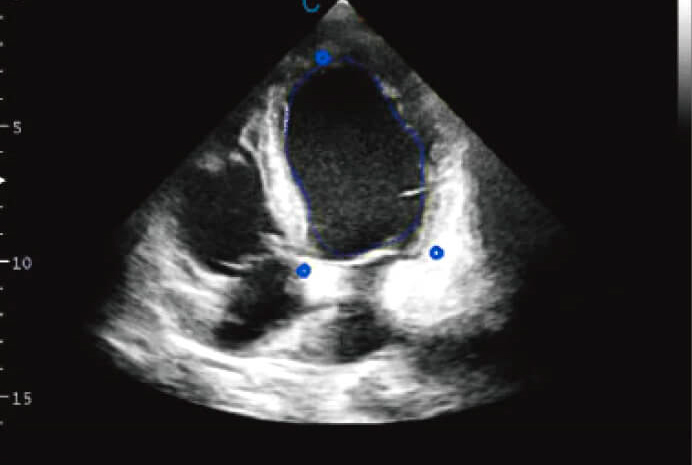

Surveillance ventriculaire gauche (VG)

- Une nouvelle méthode non invasive d'évaluation globale du ventricule gauche.

- Analyse le fonctionnement local du ventricule.

- Outil de contrôle et de suivi entre professionnel/patient